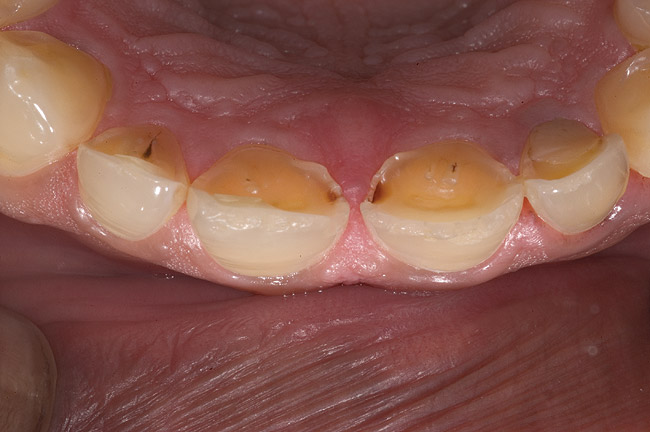

Figure 6  1:1 view demonstrating severe loss of tooth structure due to palatal erosion.

Figure 6

Figure 7  Palatal surface showing loss of form due to enamel dissolution.

Figure 7

Examination revealed that palatal surfaces of teeth Nos. 6 through 11 showed severe loss of tooth structure, with mild wear on the lower incisors and loss of anterior guidance (Figure 5 through Figure 7). The palatal TSL was consistent with the clinical picture presented by patients with gastric reflux. A detailed medical history was taken, and the patient complained of having heartburn and acidity at least 4 out of 7 days a week. He had never sought treatment for it and used over-the-counter medication when needed. He was a nonsmoker, with occasional intake of alcohol. He had a high-stress job with irregular meal times. A thorough smile and dental analysis11 was carried out; the findings appear in Table 2.